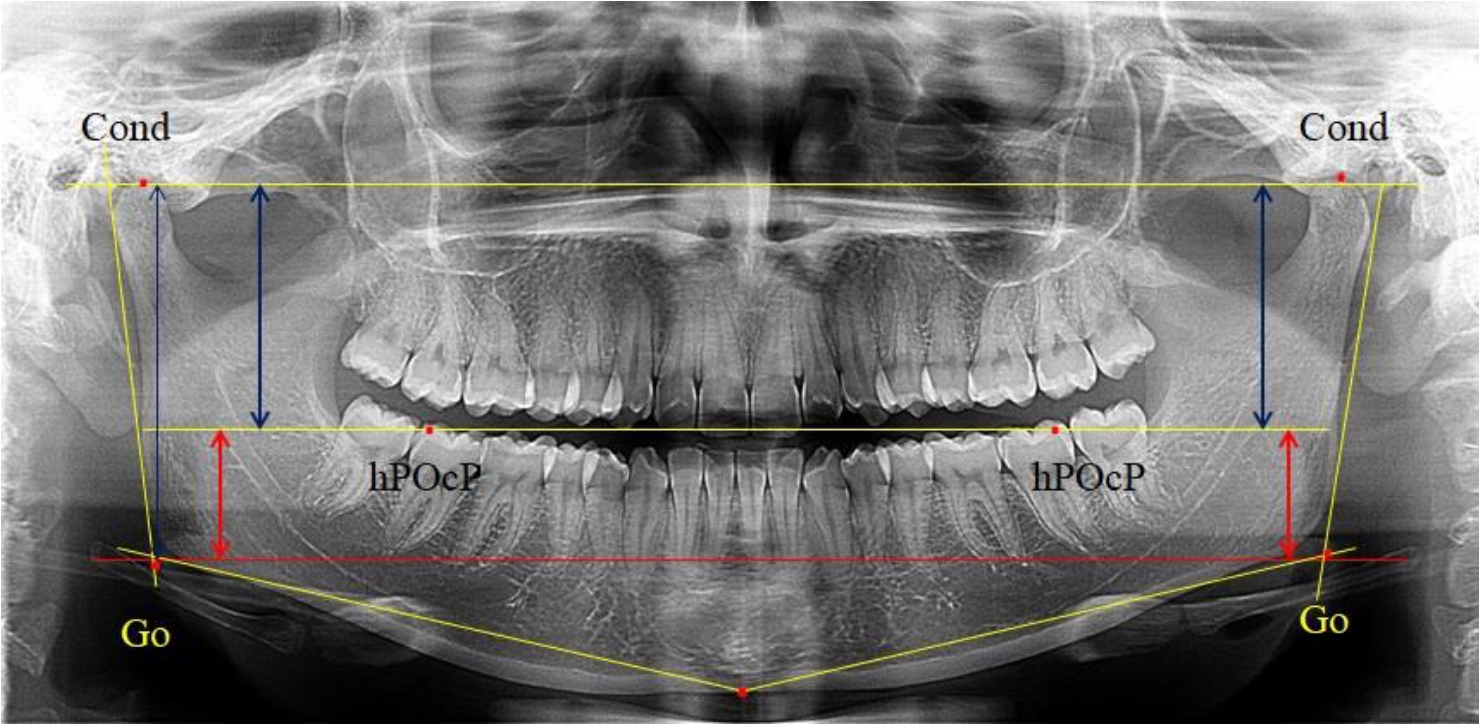

На ортопантомограмме использовали аналогичные суставные точки Cond на каждой стороне, их соединяли между собой суставной линией Cond-Cond.

Касательная к ветви нижней челюсти соединяла выступающие точку. При построении касательной к телу челюсти проводили в обе стороны линии от точки Gn, расположенной в нижней центральной части подбородочного симфиза, до выступающей нижней точки угла челюсти. Касательные линии при пересечении определяли конструктивную точку гонион Go. Соединение гониональных точек определяло положение гониональной линии Go-Go. При соединении окклюзионных точек hPOcP получали окклюзионную горизонталь (рис. 1). Измеряли расстояние между горизонталями в области ветвей нижней челюсти. Статистический анализ проводили в программе Microsoft Excel. Составляли вариационные ряды с последующим расчетом среднего значения, стандартного отклонения и ошибки среднего ±m. Также оценивали максимальные и минимальные значения величин. Определи относительные величины соотношения верхней и нижней частей ветви нижней челюсти.

Рис. 1. Метод измерения высоты ветви нижней челюсти на телерентгенограмме (а) и ортопантомограмме (б)